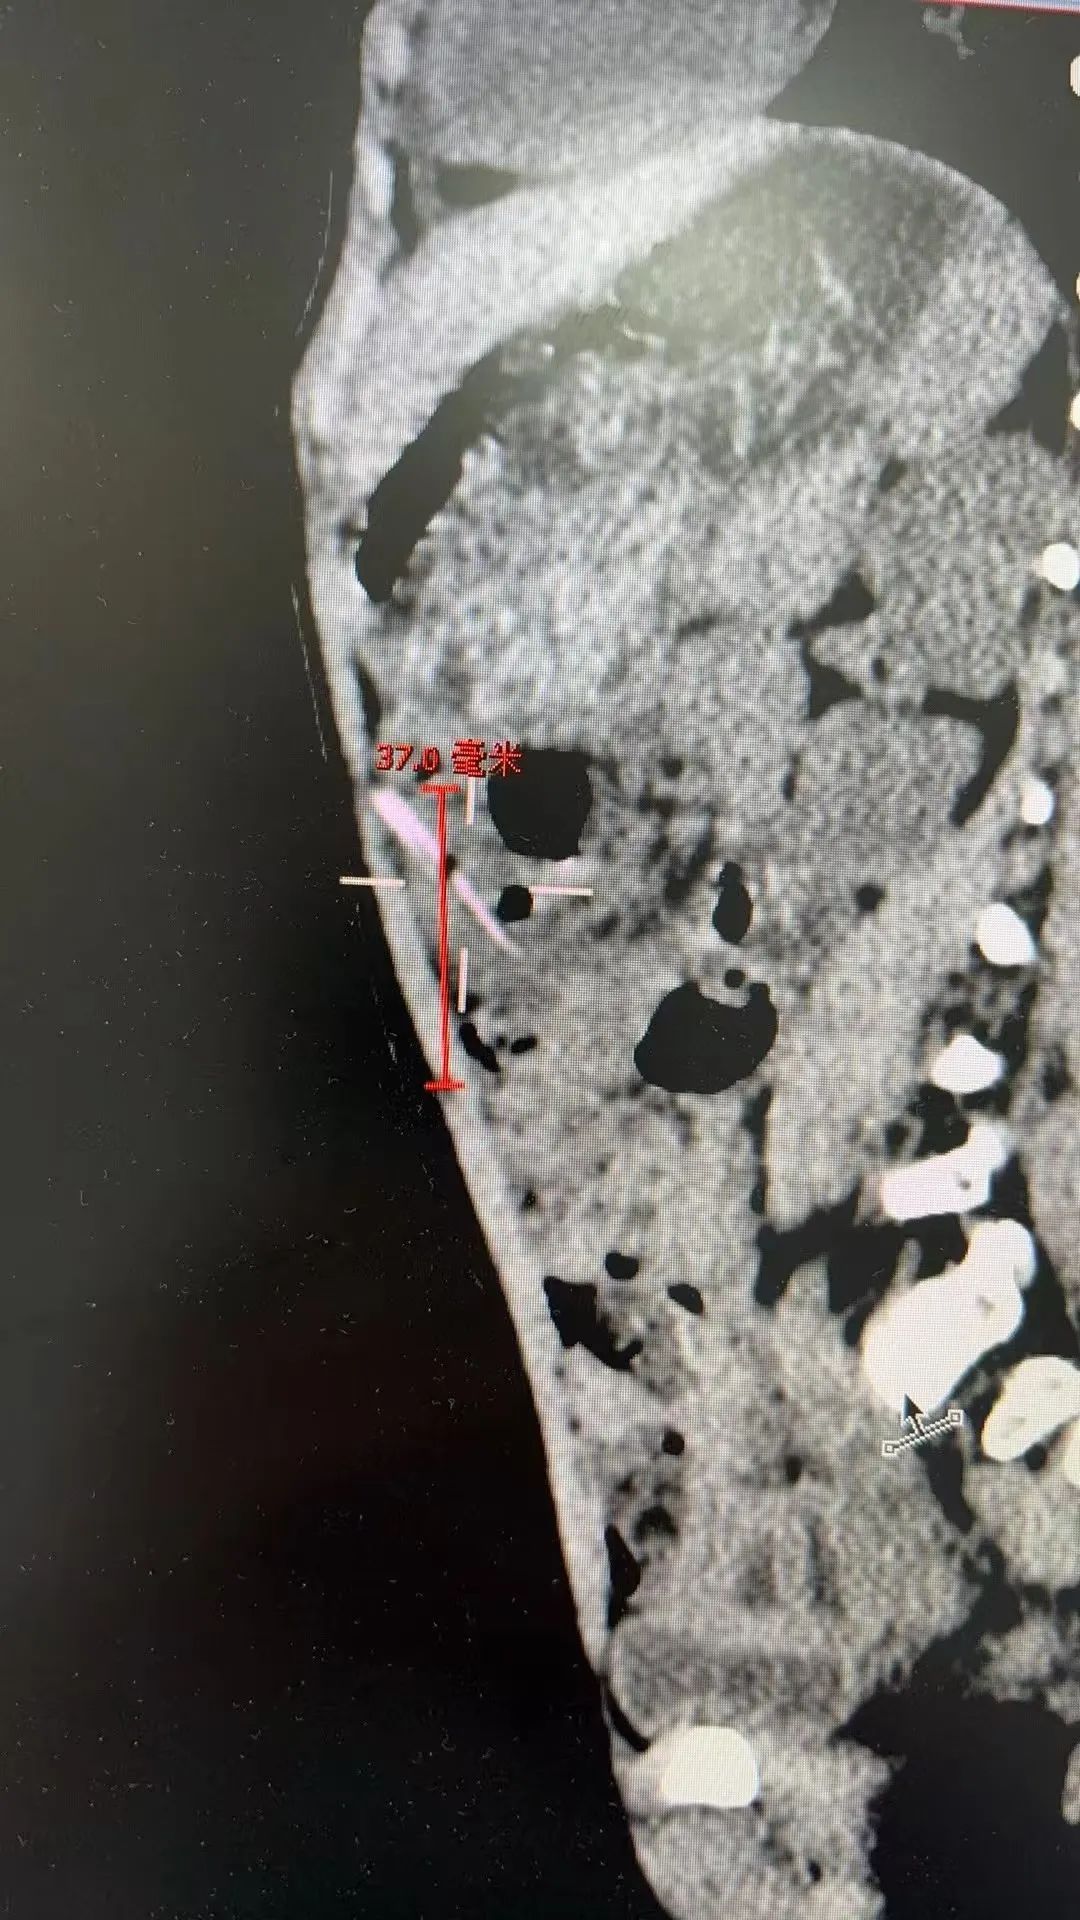

医生听添添父母讲述了病史,查看孩子并无感冒症状,推测腹痛很有可能与误食异物有关,随后的腹部CT检查发现孩子腹腔内疑似存在约2.5厘米长的异物,医生立即建议孩子住院治疗。

入院后,添添的症状有所好转,父母抱着或许能自己排出的期待,希望暂缓手术继续观察,可是两天后复查CT,异物还在宝宝的肚子里纹丝未动。

为了避免延误治疗,医生为添添实施了腹腔镜微创手术。术中探查结果令人心惊:一根长约2~3厘米的尖锐竹签,已穿透患儿肠管,深深刺入腹腔。万幸的是,竹签未伤及其他重要脏器,也未引发严重感染。